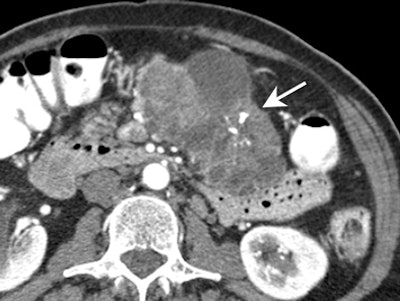

![]() |

| Mucinous cystadenocarcinoma. Presence of mural calcifications (arrow) and septations are suggestive of malignancy. |